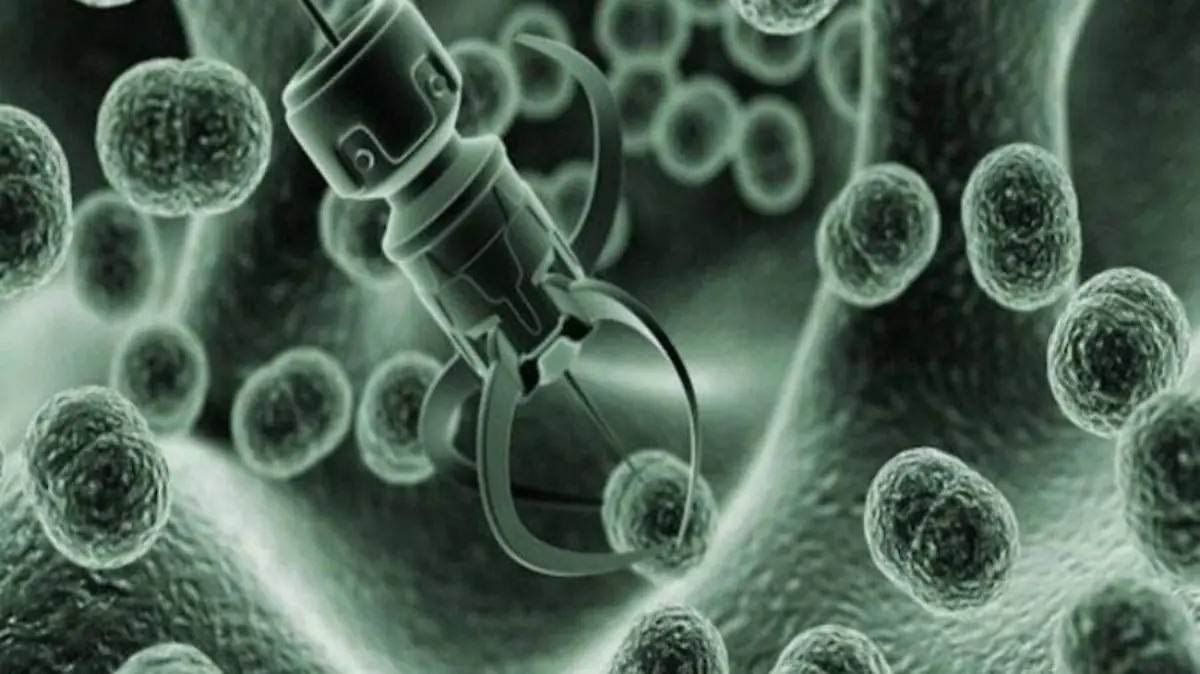

Urge utilizar “robots” para ayudar a instituciones de salud

Plantean aplicar inteligencia artificial en la medicina para responder a la demanda.

Plantean aplicar inteligencia artificial en la medicina para responder a la demanda.